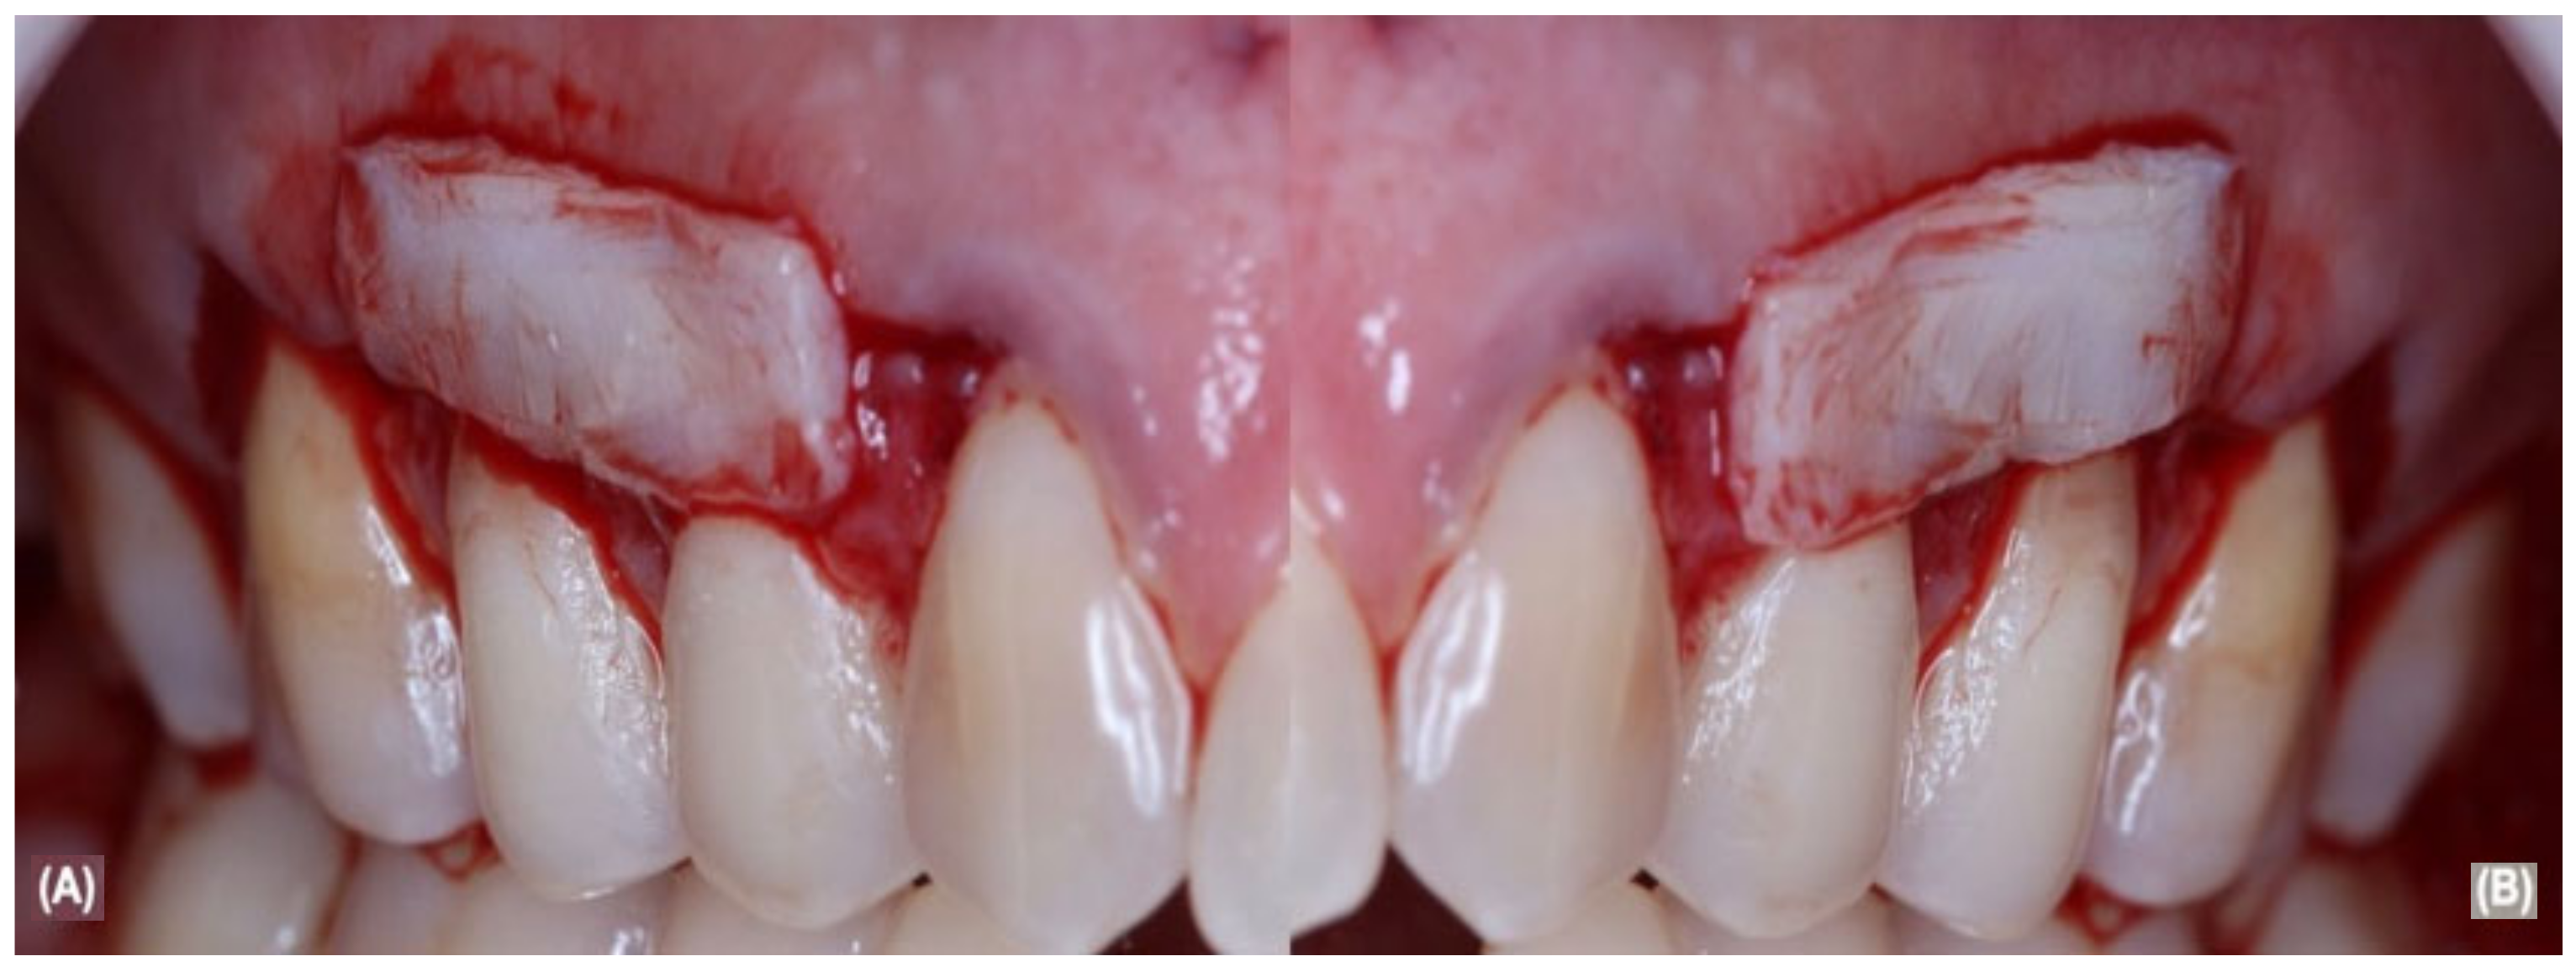

2.5. Periodontal Surgical and Post-Operative Treatment